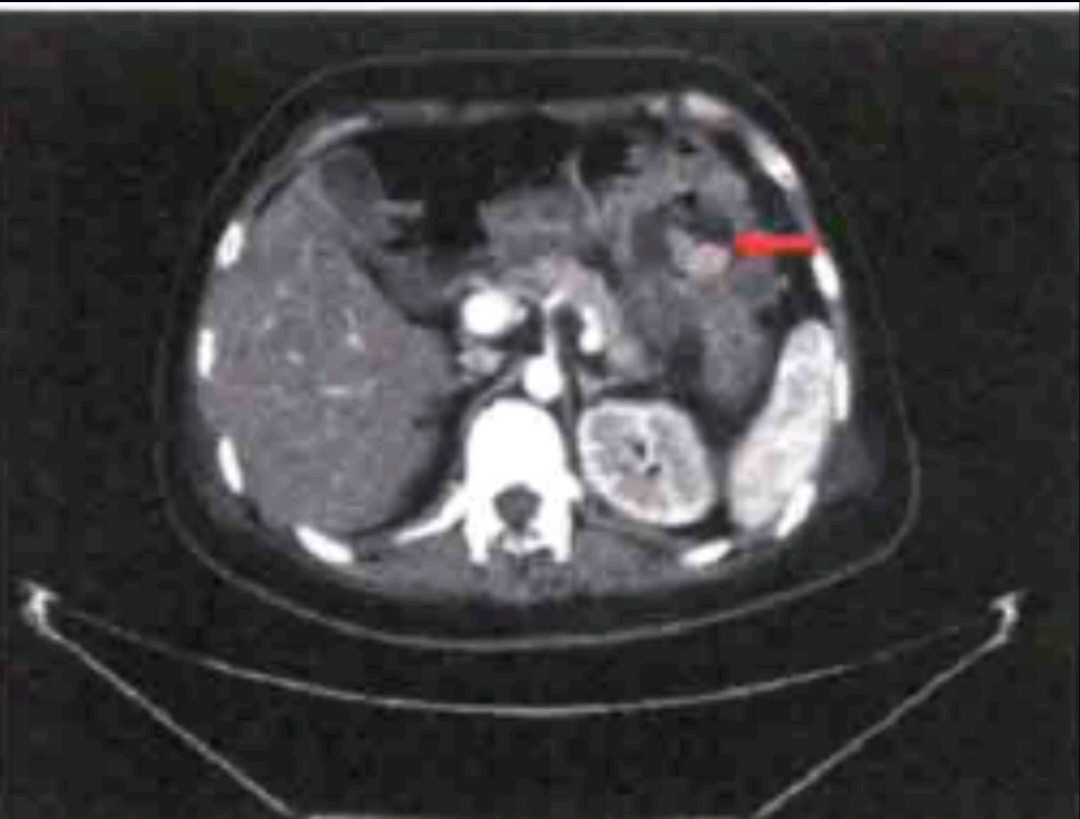

辅助检查:腹部增强CT示:左上腹腔内结构紊乱,可见团状含气软组织密度影,增强后呈不均匀强化,边界不清,局部与胃体部分界不清, 似与横结肠及降结肠相通,病灶周围可见游离的气体影,相邻脂肪间隙模糊(图箭头所示为疑似的胃结肠瘘)。

入院后为明确诊断,完善相关检查:血常规: WBC 10.10x 10*/L, Hb 50gL;白蛋白22g/L; 其余大致正常。腹部增强CT示:左上腹腔内结构紊乱,可见团状含气软组织密度影,增强后呈不均匀强化,边界不清,局部与胃体部分界不清, 似与横结肠及降结肠相通,病灶周围可见游离的气体影,相邻脂肪间隙模糊(图箭头所示为疑似的胃结肠瘘)。上消化道造影提示:胃体部大弯侧不规则龛影、造影剂进人横结肠,考虑占位病变、并胃-结肠瘘形成可能大。结肠造影显示:考虑占位病变降结肠近脾曲管腔狭窄、可疑充盈缺损,造影剂未通过并梗阻性表现可能大。胃镜检查:胃体小弯侧偏前壁巨大深溃疡,见污秽苔,透过瘘管可见横结肠内粪便,周围黏膜明显充血水肿,组织易出血。病理结果考虑胃体小弯侧胃黏膜腺癌浸润。考虑该例患者肿瘤分期晚,可能难以达到根治性切除,术前营养状况及基础条件差,入院时血常规、血生化示血红蛋白42g/L、白蛋白22 g/L,存在重度贫血及低蛋白血症;术前输注同型红细胞10 U,血红蛋白上升至106g/L,同时经过术前积极的全肠外营养支持治疗后营养状况有所好转,白蛋白35 g/L,患者诊断胃癌明确,有手术指征,未见明显手术禁忌症,遂行了姑息性远端胃大部切除术、横结肠部分切除术(近端造口,远端封闭)、胃空肠吻合(Roux- -en-Y)、空肠-十二指肠侧侧吻合术。术中探查见胃体前壁近大弯侧可触及约8 cm质硬肿物,肿物侵及横结肠并形成胃结肠瘘。胃周及后腹膜可触及多枚质硬肿大淋巴结,部分融合固定,切除病灶后行胃空肠吻合( Roux- -en-Y)。病理提示胃壁全层低分化腺癌浸润,脉管内见癌栓,术后第一天进流质饮食,逐步过渡半流质,术后一周出院。